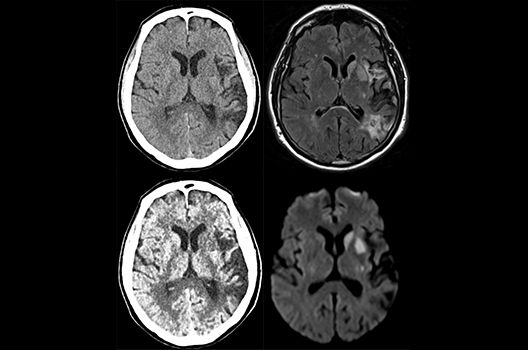

Die Schwerpunkte in der CT-Forschung liegen in der Bildnachverarbeitung, der Dosis- und Artefaktreduktion sowie der quantitativen und automatisierten CT-Bildanalyse.

Die Computertomographie (CT) ist ein Verfahren, bei der mit Hilfe von Röntgenstrahlung Schnittbilder des Körperinneren angefertigt werden. Unser Bestreben ist es hierbei, bei möglichst niedriger Strahlendosis eine bestmögliche Bildqualität zu erzielen. Eine zunehmend große Rolle in der radiologischen Forschung spielen zudem die Automatisierung in der Bildanalyse und die computergestützte Auswertung großer Datenmengen, wie sie bei einer CT-Untersuchung anfallen. Wir arbeiten in enger Kooperation mit den Geräteherstellern zusammen und sind daher maßgeblich an der Entwicklung und Erprobung neuer Techniken beteiligt.

Die Schwerpunkte in der MR-Forschung liegen in der multiparametrischen und funktionellen Bildgebung bei onkologischen und anderen, neuroradiologischen Fragestellungen und umfassen die Anwendung modernster MR-Verfahren sowie die Untersuchung an Hochfeld-Geräten.

Die Magnetresonanztomographie (MRT) ist ein Verfahren, bei dem durch magnetische Kräfte Bilder des Körperinneren angefertigt werden. In der Neuroradiologie können manchmal kleinste Veränderungen schwere Folgen haben; daher forschen wir an der Entwicklung hochauflösender MRT-Sequenzen, mit denen diese Prozesse und auch einzelne Nervenfaserbahnen sichtbar gemacht werden können. Darüber hinaus sind bei vielen Erkrankungen des Gehirns die Blutgefäße betroffen. Daher arbeiten wir an der Neu- und Weiterentwicklung von MRT-Sequenzen zur Darstellung der Blutgefäße und zur Blutflussanalyse (sog. „Angio-MRT“). Einen besonderen Forschungsschwerpunkt unserer Klinik stellen die MR-Protonenspektroskopie und die funktionelle MRT dar, mit denen die Analyse einzelner chemischer Substanzen im Hirngewebe oder die Darstellung ausgewählter Hirnfunktionen möglich ist.